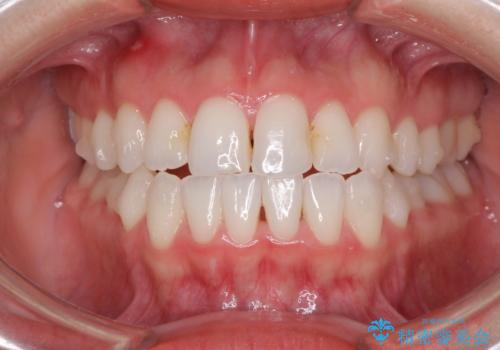

前歯のクロスバイトを治したい インビザラインによる矯正治療

- 前歯のデコボコとクロスバイトを治したいとのことで来院された患者様です。

上下顎ともに歯列全体の側方拡大とIPR(歯と歯の間を削る)によってデコボコとクロスバイトが解消するように設計し、インビザラインにより治療を行うこととしました。

下顎骨の左側への骨格的なずれが強く、上下の正中の位置合わせや奥歯の咬み合わせ構築に苦労しました。